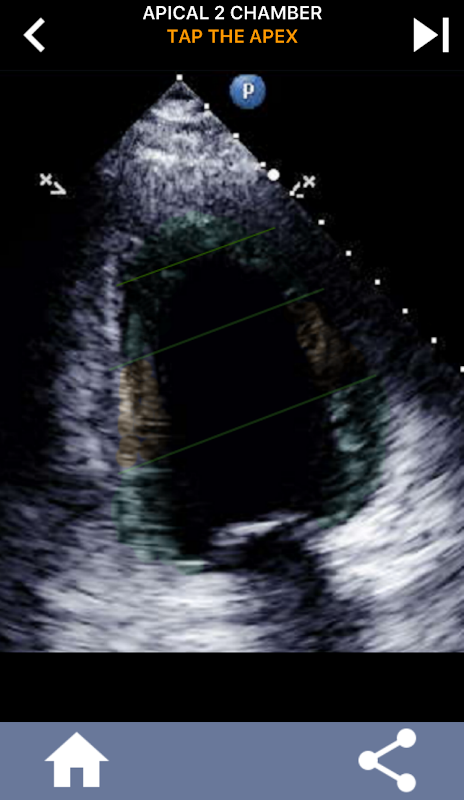

Deze app bevat alle echoviews die het AHA-gesegmenteerde myocardium tonen en zal je vragen het juiste segment te tikken. Persoonlijk vind ik dat repetitieve quizzing het beste werkt voor mij als ik het onderwerp snel moet leren / onthouden. Als je een echografie-student bent die echo / TTE studeert, denk ik dat dit een uitstekende aanvulling op je studie zou zijn.